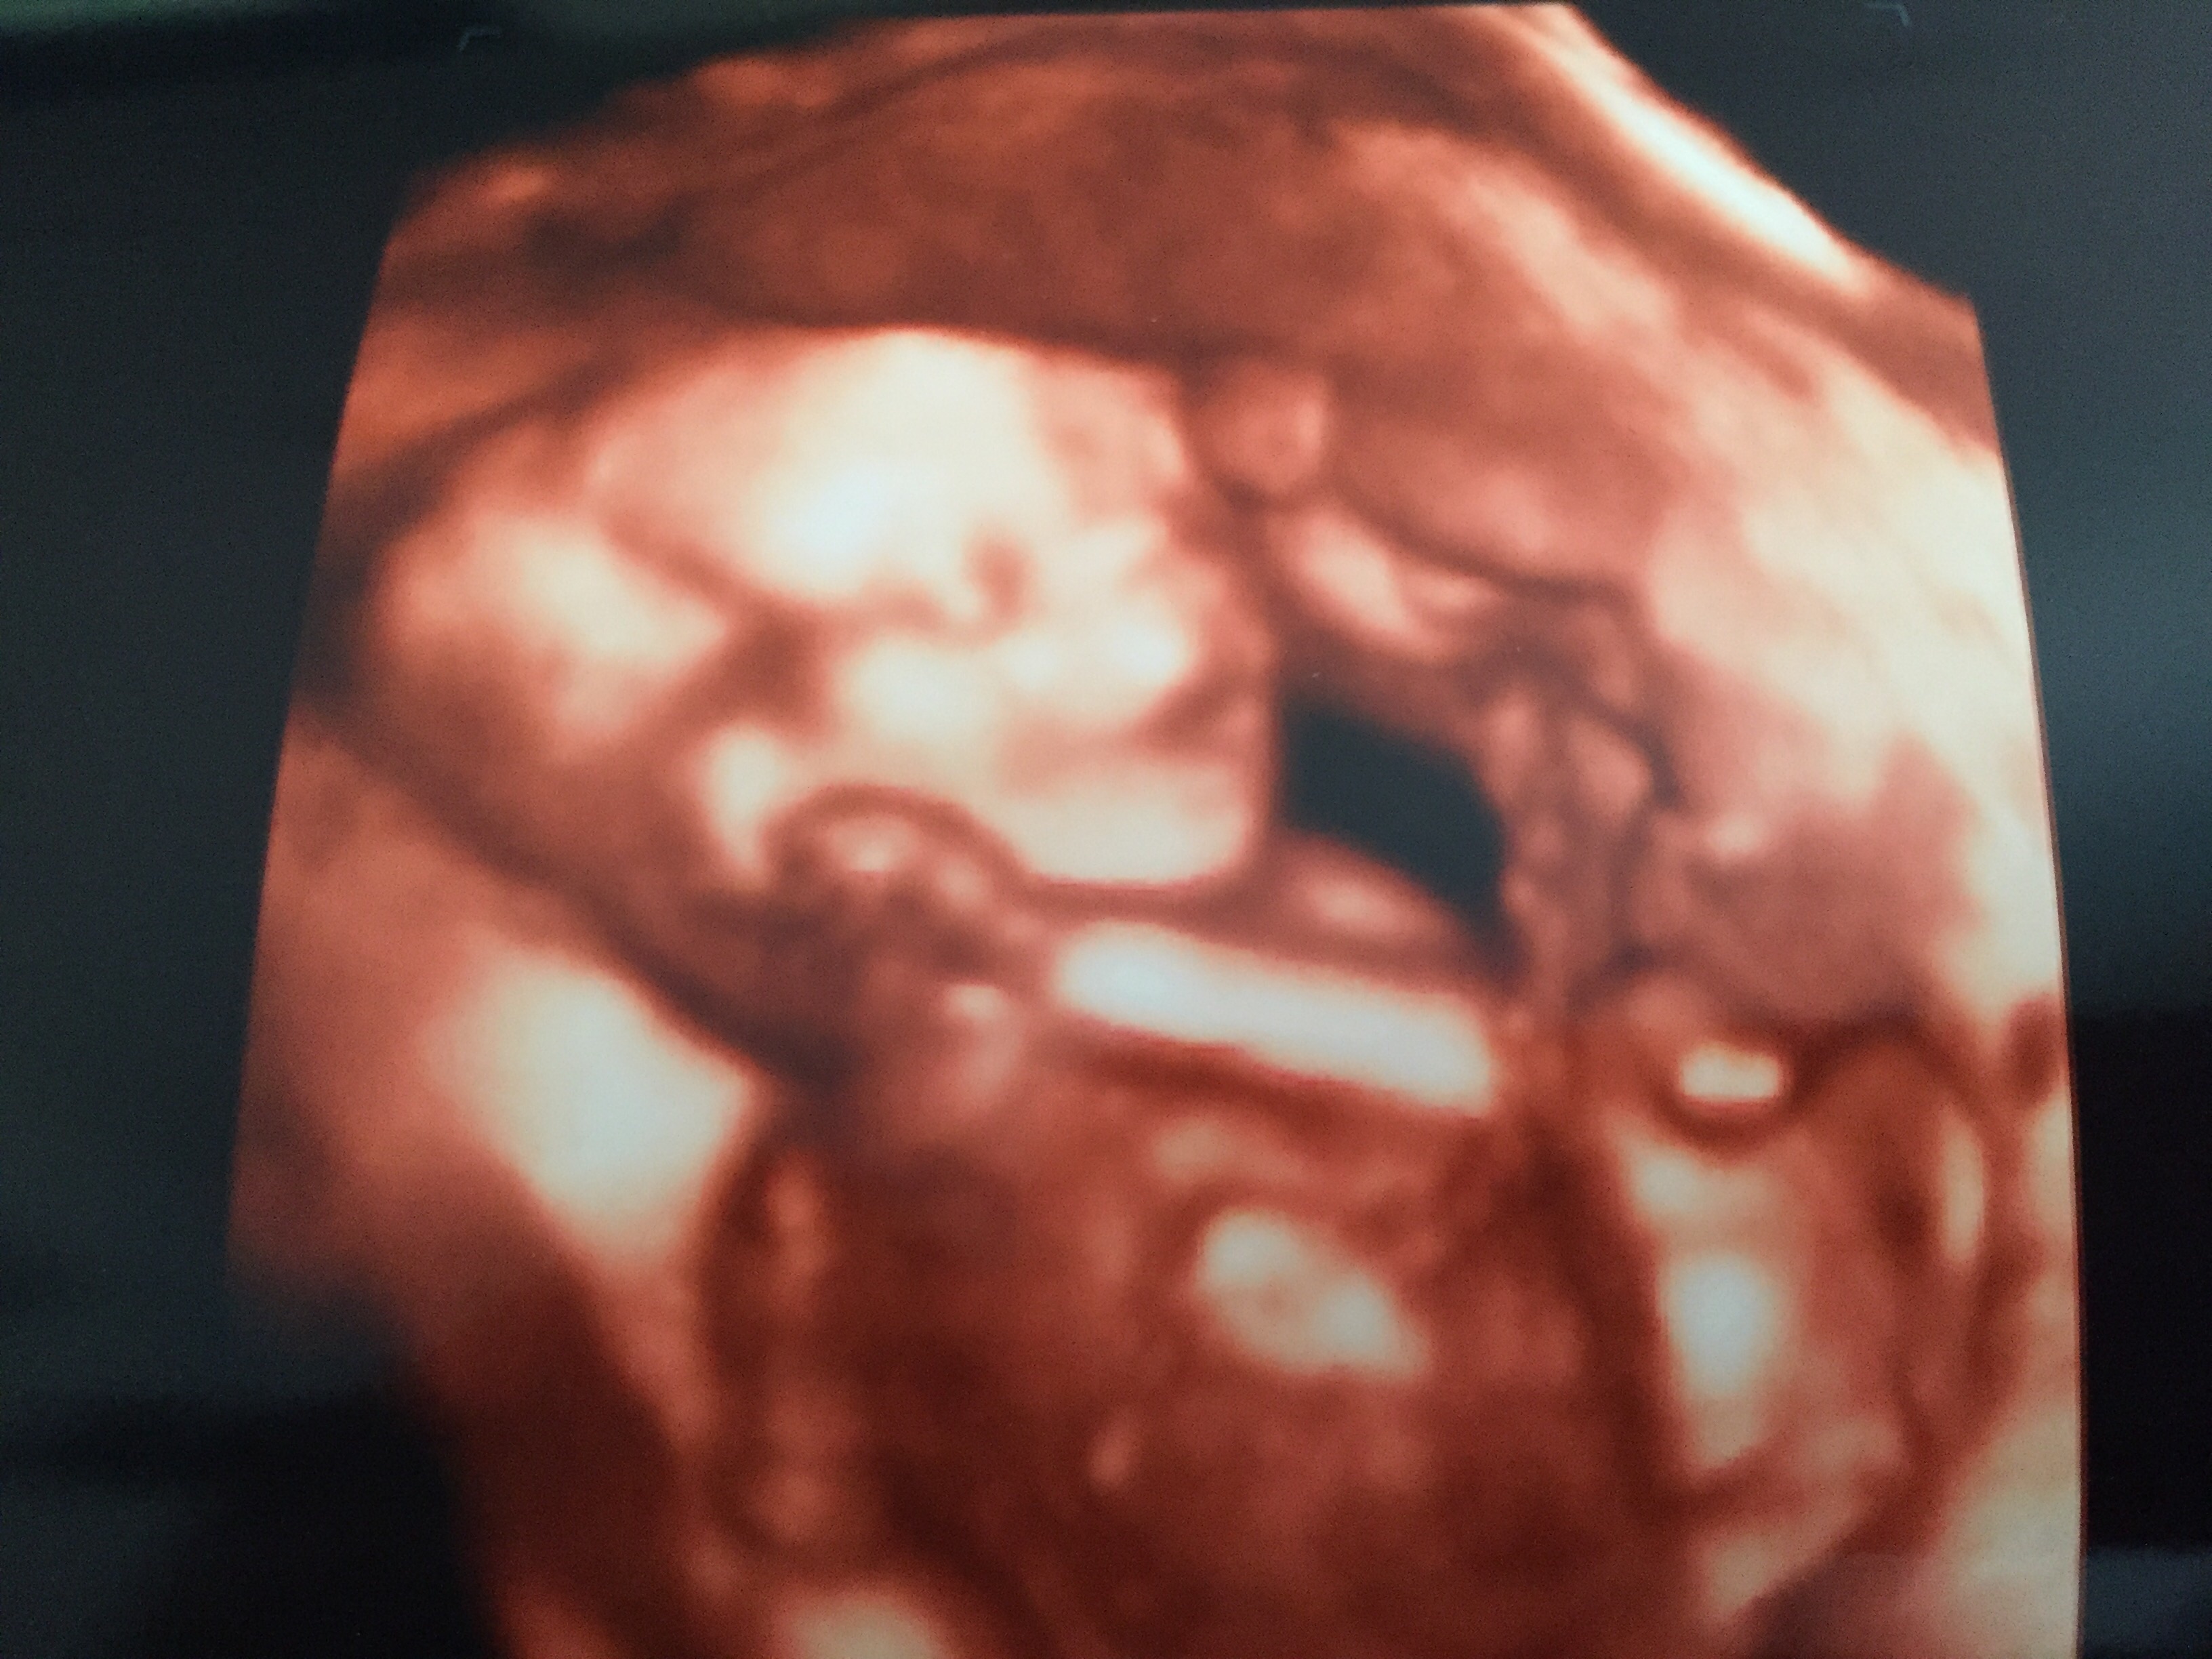

We are having a boy!!!! He is so cute. All of the half siblings that we know of are girls. First precious little boy. The 3D pics are amazing and we had a great sonographer who made us feel right at home.

@jambrown1516 how precious! He does look like he's smiling!! I love those 3d ultrasounds...I wonder if they have that available at my drs office! I just found out last week that I have to go see a MFM (maternal fetal medicine specialist) bc of my vanishing twin. They will also be doing an ultrasound at 20 weeks (my anatomy scan is 17 weeks). I would assume they will have more high tech sono machines than my OBs office! I'll be excited either way to see the baby twice in once month